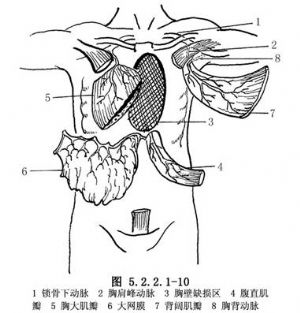

胸大肌瓣(pectoralis major muscle flaps):血運供應來自胸肩峯動脈和內乳動脈的肋間穿支,留其中之一即可保證血運。適於腋中線以前至胸骨處胸壁缺損,亦可用於胸腔內轉移肌瓣(圖5.2.2.1-10,5.2.2.1-11)。

背闊肌瓣(latissimus dorsi muscle flaps):血運主要由胸背動脈或肋間動脈和腰動脈穿支節段性供應。該肌瓣用於前側胸壁缺損重建。該肌瓣自根部切斷向後下反轉,保留動脈穿支,修補胸廓下部脊柱旁的胸壁缺損(圖5.2.2.1-10,5.2.2.1-11)。

腹直肌瓣(rectus abdominis muscle flaps):供應血管主要爲腹壁上血管。該肌瓣用於修復前胸壁和側胸壁缺損(圖5.2.2.1-10)。